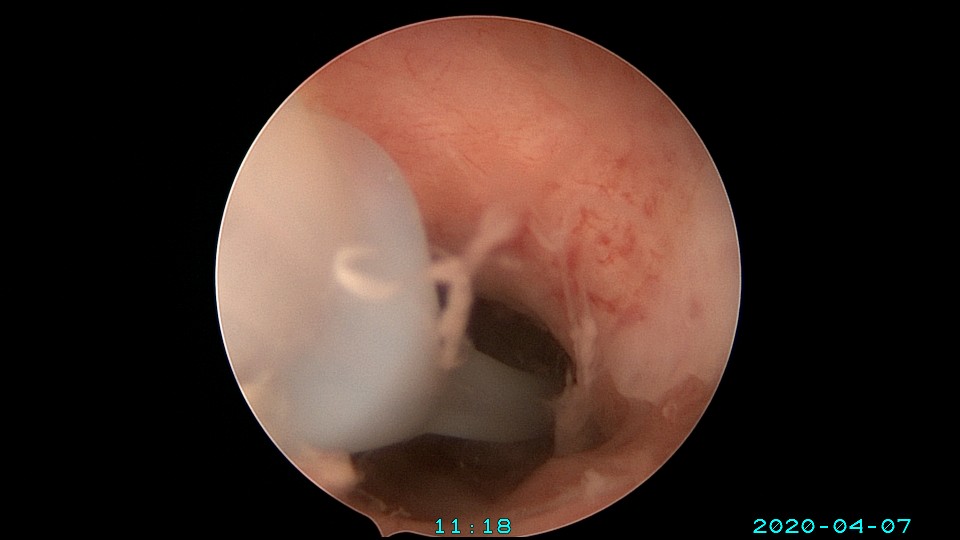

患者36岁,G3P0,自然流产3次,发现宫腔粘连3个月。2020年3月宫腔镜探查,子宫前倾后屈位,宫深8.5cm,宫颈管粘连狭窄,扩宫进入宫腔,见宫腔中下段两侧壁粘连,剪刀及双极电切分粘,宫腔形态恢复正常,双侧输卵管开口显露。2020年4月宫腔镜二探取球囊,宫腔形态正常,双侧输卵管开口可见。2021年6月自然妊娠,2022年2月足月剖宫产分娩。现42岁,G4P1。